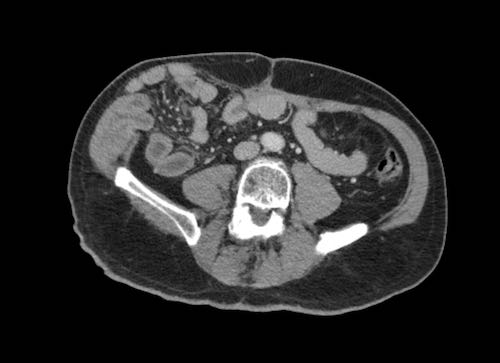

Hình ảnh

Hình ảnh CT của một bệnh nhân ung thư phúc mạc.

Một lượng nhỏ dịch cổ trướng hiện diện ở góc phần tư trước bên phải.

Các đường dày dạng nốt vuông góc với thành ruột được ghi nhận.

Hình ảnh này đại diện cho tổn thương xâm lấn mạc treo ruột lan rộng (mũi tên).